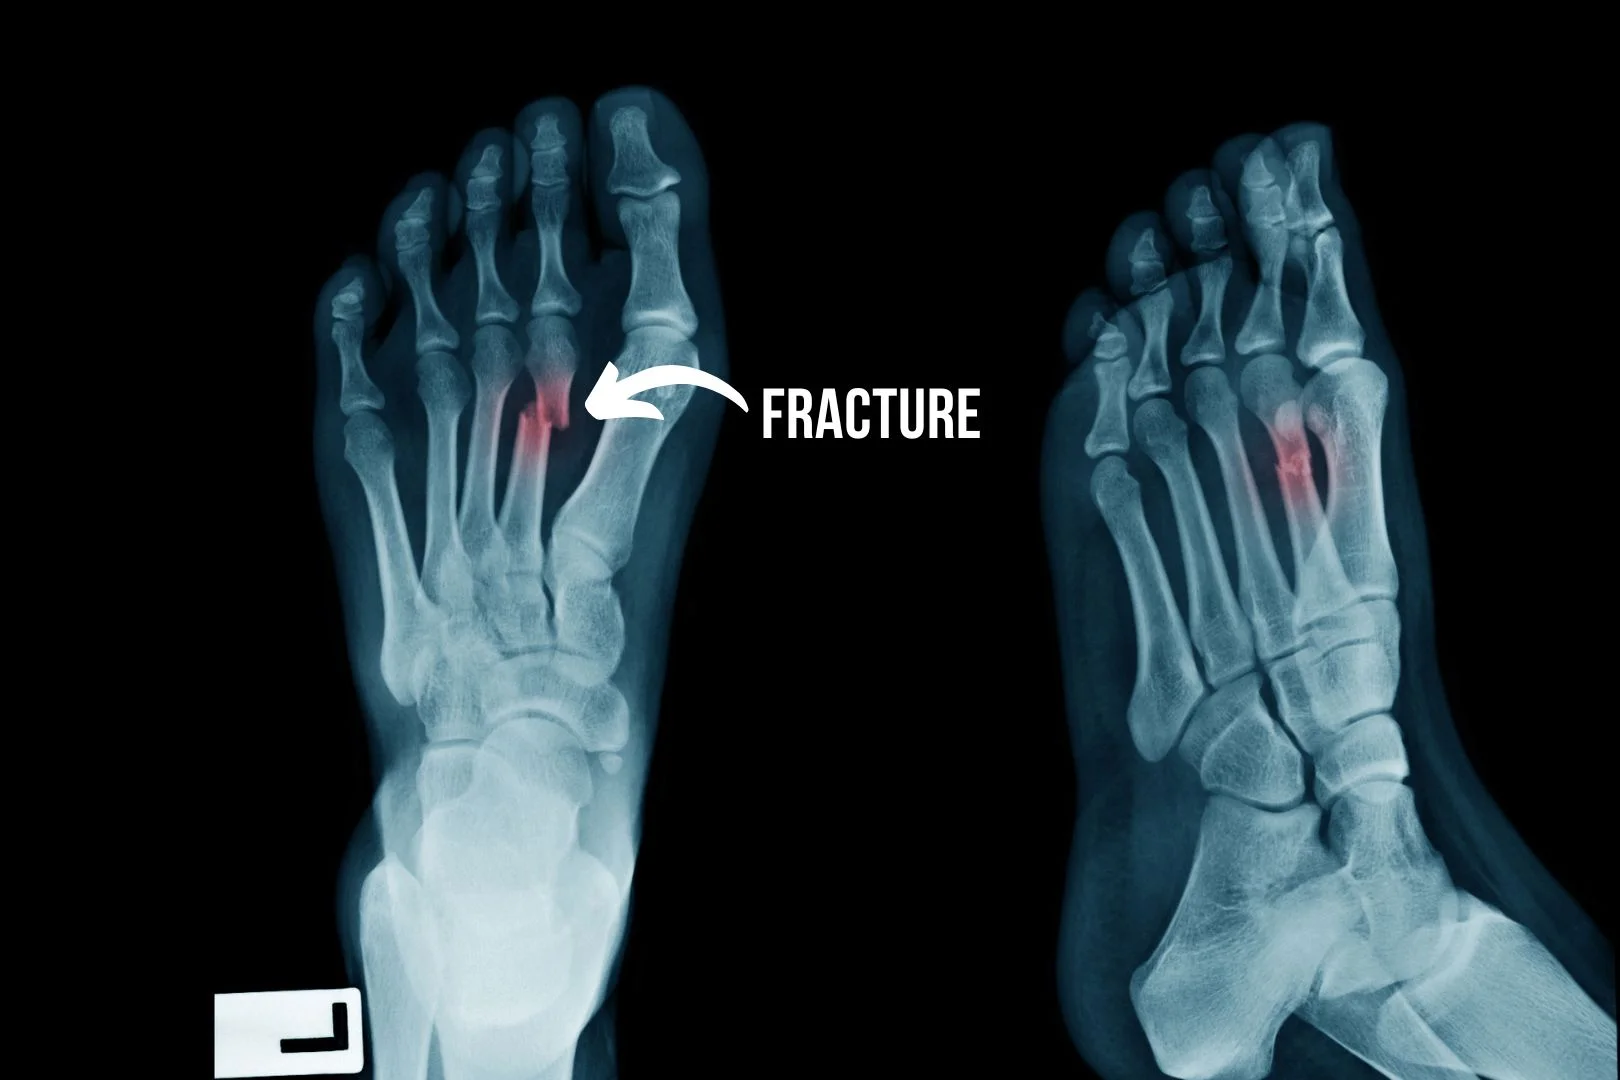

X-ray showing complete fracture of left second metatarsal bone